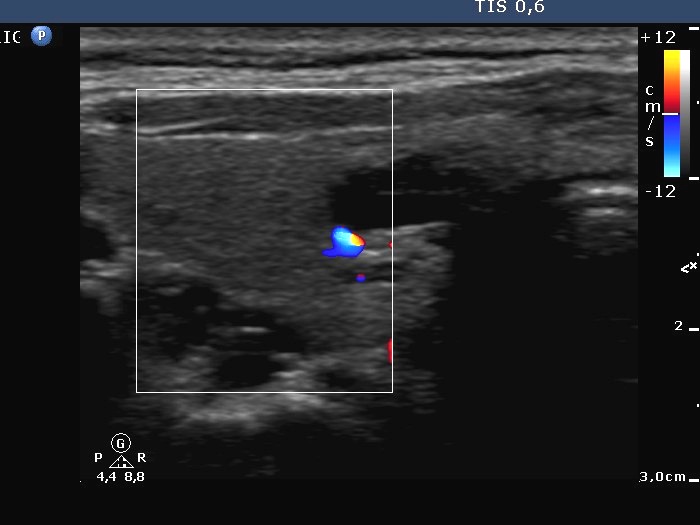

Follow-up investigation 17 months after the first visit (ultrasonographic picture 3)

Right lobe, transverse scan, color Doppler method. The vascularization is decreased.